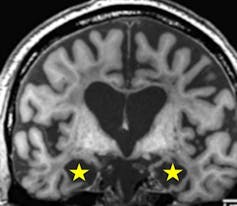

Imagen de resonancia del cerebro de H.M. donde se aprecia la ausencia de sus hipocampos .

McCormick et al., 2018.

Tras la cirugía, H.M. se curó de su epilepsia, pero desarrolló una incapacidad de generar nuevos recuerdos (amnesia anterógrada). Brenda Milner, quien lo trató durante las décadas subsiguientes, tuvo que presentarse a él de nuevo cada mañana.